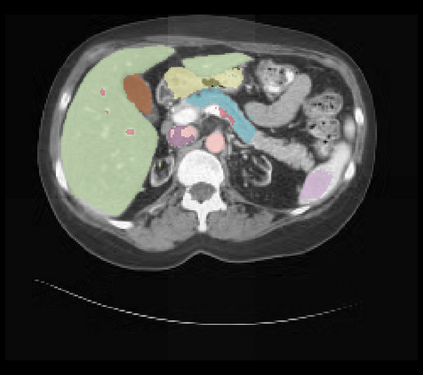

It is imperative to ensure the robustness of deep learning models in critical applications such as, healthcare. While recent advances in deep learning have improved the performance of volumetric medical image segmentation models, these models cannot be deployed for real-world applications immediately due to their vulnerability to adversarial attacks. We present a 3D frequency domain adversarial attack for volumetric medical image segmentation models and demonstrate its advantages over conventional input or voxel domain attacks. Using our proposed attack, we introduce a novel frequency domain adversarial training approach for optimizing a robust model against voxel and frequency domain attacks. Moreover, we propose frequency consistency loss to regulate our frequency domain adversarial training that achieves a better tradeoff between model's performance on clean and adversarial samples. Code is publicly available at https://github.com/asif-hanif/vafa.